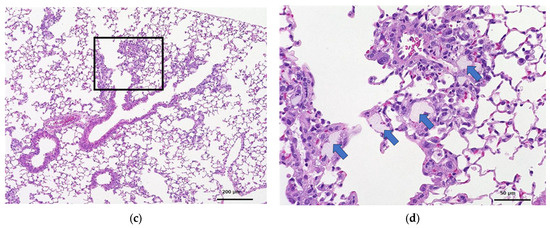

Histopathological Examination

- No abnormalities were observed at necropsy; histopathologic examination consistently showed a moderate accumulation of alveolar macrophages in all cases at 3 and 28 days after administration. These changes were interpreted as adaptive responses to the intratracheal administration of the test compound.